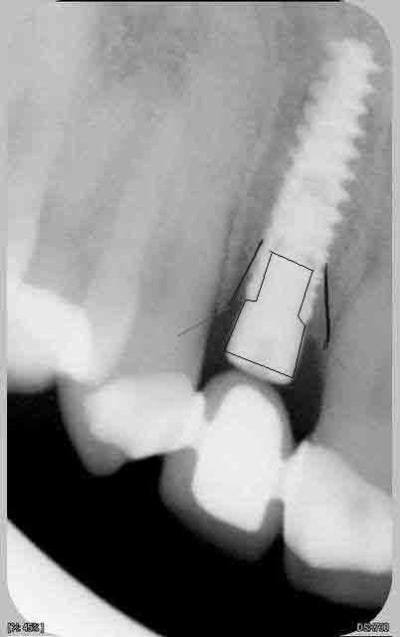

nouvelle radio cette semaine

c'est des krestals? Ça n'a pas l'air dramatique sur la radio. Une petite caractérisation qui me parait logique vu la connexion.

> c'est des krestals? Ça n'a pas l'air dramatique sur la radio. Une petite

On n'a pas les mêmes critères d'exigences. Perdre 4 mm d'os sur 12 soit 1/3.

Attends, sur ces radios t'as 4 mm de perte osseuse? Les vis de cicatrisation sont en place non? Je devine la jonction implant/vis et y a quasiment pas de perte sur tes dernières radio. Enfin je connais pas bien le krestal et la forme de la vis.

Je veux dire, elle est où la perte osseuse sur cette radio? Mais tu as raison, on ne doit pas avoir les même exigences.

chatondecarte écrivait:

La cratérisation est visible beaucoup plus haute: surtout au sondage. L'os que tu vois est en palatin, en vestibulaire, il n'y a plus rien sur cette même longueur.

Sur la molaire, tu ne vois rien aussi.

Je disais juste que je ne voyais rien d'affolant sur la radio, mais bien sur si tu as 4mm au sondage, c'est ça qui prime.